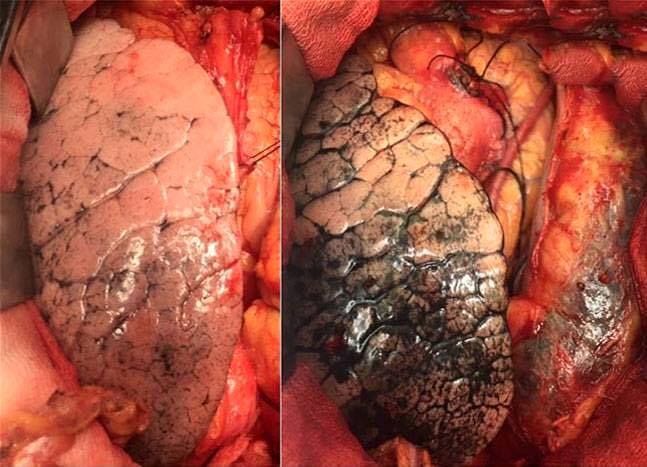

বায়ু দুষন সহ সকল ধরনের পরিবেশ দুষন যে আমাদের শরীরের জন্য ক্ষতিকর এটা আমরা সবাই জানি। কিন্তু কোন ধরনের দুষনে আমাদের শরীরের কিভাবে কতটা ক্ষতি করে সেটা কি আমাদের সবার জানা আছে? দুষন মানব দেহের ফুসফুসের কিভাবে ক্ষতি করছে ভারতের এক গবেষক এ সংক্রান্ত দুটি ফুসফুসের ছবি প্রকাশ করেছেন যা দেখলে সত্যিই গা শিহরে উঠে। নিচের দুটি ফুসফুসের ছবির দিকে ভাল করে লক্ষ্য করুন, আর এ সংক্রান্ত বর্ননা নিচে দেয়া হল-

►মানুষের ফুসফুসের ছবি দুটির দিকে লক্ষ্য করুন। ভারতের একজন বিখ্যাত ডাক্তার Dr Naresh Trehan ছবি দুটি তুলেছেন।

►বামপাশের পরিষ্কার ছবিটি ভারতের হিমাচল প্রদেশের ৫৫ বছর বয়সী ব্যাক্তির। আর ডান পাশের দুষিত ও বিভৎস ছবিটি দিল্লীর ৫২ বছর বয়সী একজন ব্যাক্তির।

►দিল্লীর প্রচন্ড বায়ু দষনের কারনেই ডানের ৫২ বছর বয়সী ফুসফুসের ছবিটি এরকম দুষিত ও বিভৎস। অথচ বৃক্ষরাজী ঘেরা হিমাচলের বাম পাশের ফুসফুসের ছবিটি ৫৫ বছর বয়সেও কত সজীব।